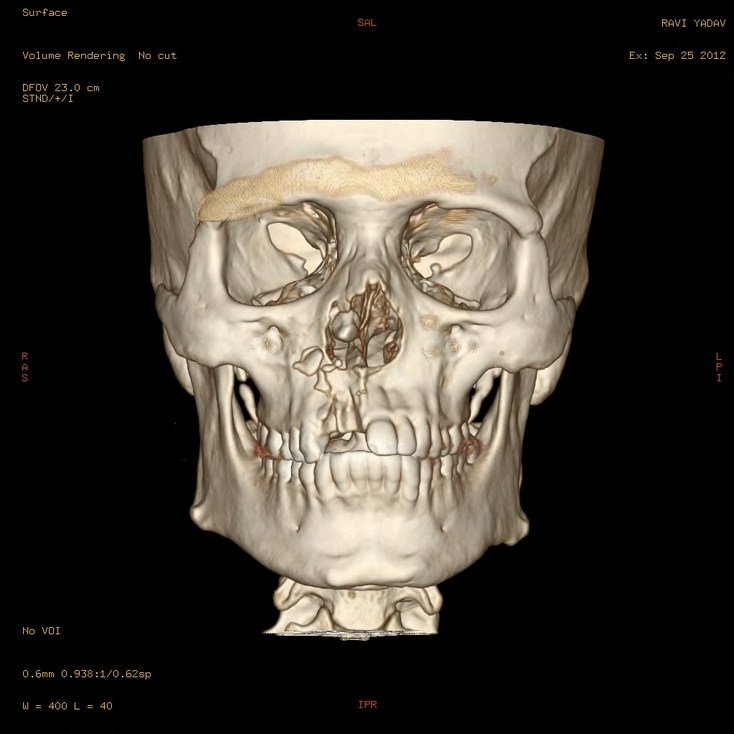

3D CT Facial Bones